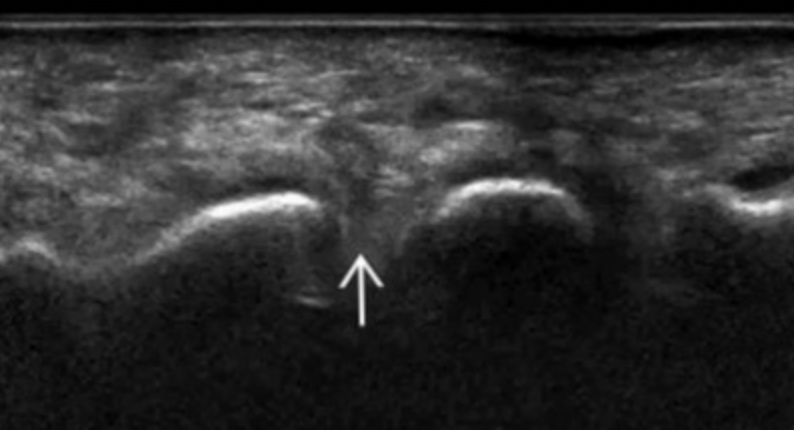

Morton Neuroma

• Mulder sign - pain when squeezing the metatarsals